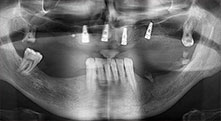

Professor Dr Emanuel Bratu, maxillofacial surgeon, oral surgeon and prostheticist, is head of the implantology departments at two Romanian Universities. He runs a renowned private hospital in Timisoara and is an internationally known researcher. In the interview Bratu explains why he considers that the W&H Piezomed piezosurgical device, and particularly two patented saws, have become essential for bone surgery.

For what indications do you use the saws?

Bratu: We routinely use the instruments for harvesting bone blocks and splitting alveolar ridges. We also use the Piezomed B6/B7 for osteotomy of impacted teeth and removing failed implants. All indications that require deep, clean cuts.

Could you describe briefly, for example, your procedure for mobilizing bone blocks for transplantation?

Bratu: We prefer to harvest bone from the external oblique ridge of the posterior mandible, not from the interforaminal region. After the soft-tissue incision, we use the new saws to define the amount of bone to harvest. With this approach, we also use them for the entire preparation in almost 80% of cases. We may also use other piezo instruments and then at the end a chisel to mobilize the block. We find that this is a very effective surgical technique.